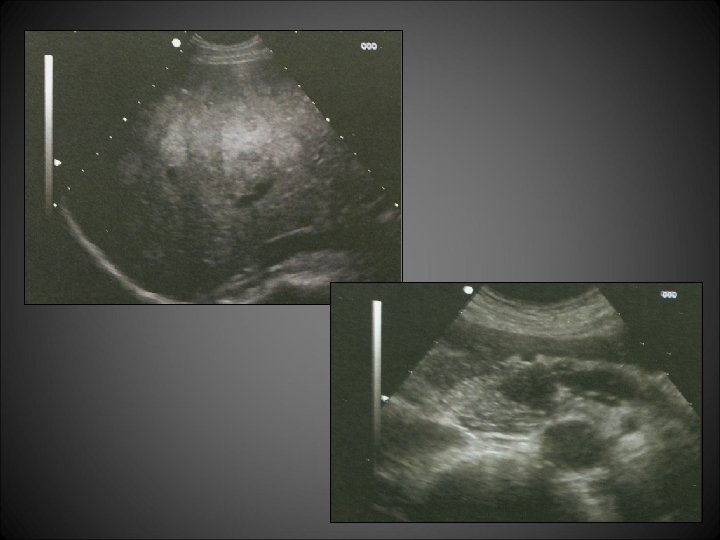

Cas n° 1 • Echographie pour bilan d’épigastralgies: Foie multinodulaire Nodule pancréatique isthmique avec dilatation du canal pancréatique d’amont • Excellent état général • Biologie: bilan hépatique et pancréatique normal élévation sérique de la sérotonine et chromogranine A • Biopsie hépatique: Métastase hépatique d’un carcinome endocrine bien différencié, exprimant Chromogranine A et synaptophysine